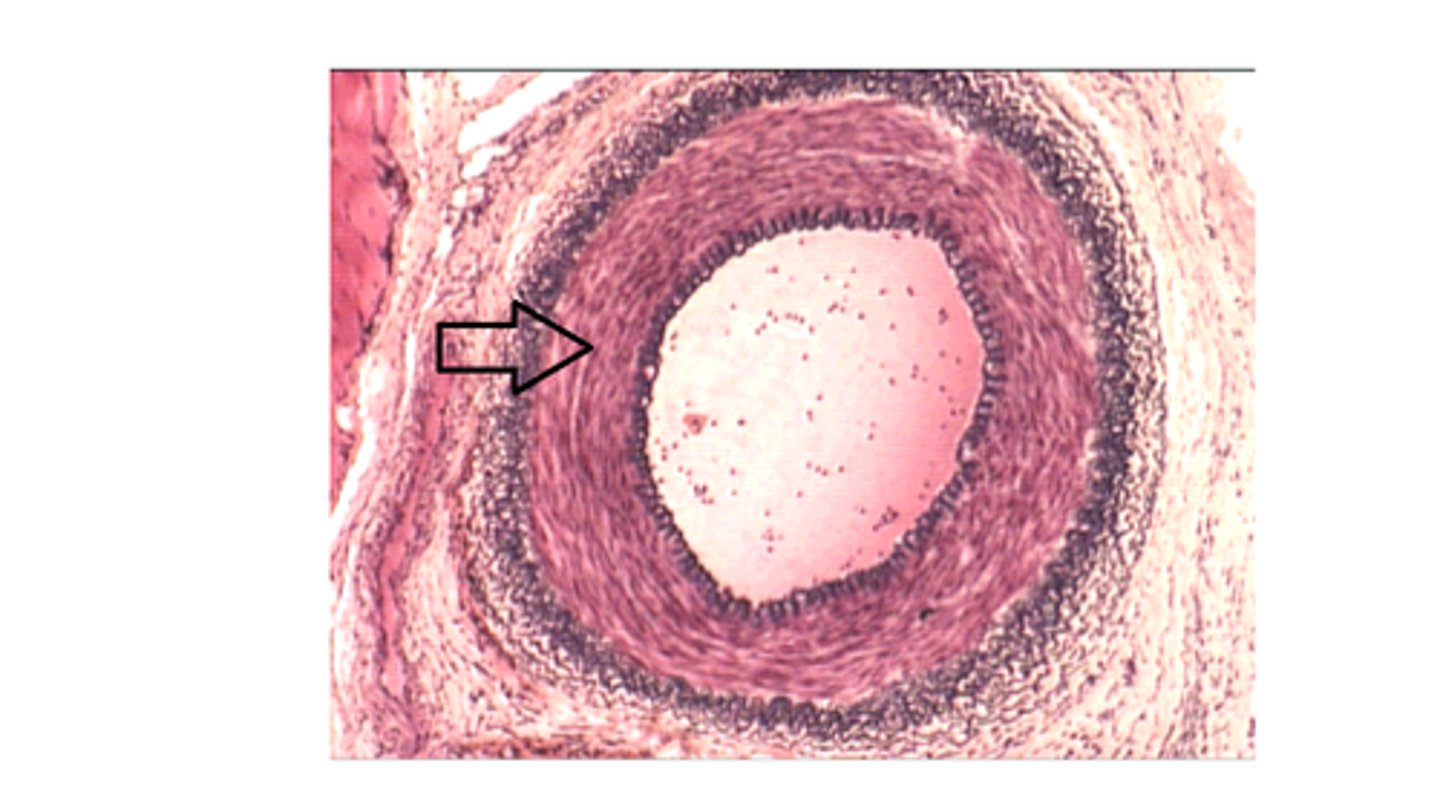

medium size (muscular) artery

ID the tissue

Tunica media of a medium size artery

The arrow is pointing at